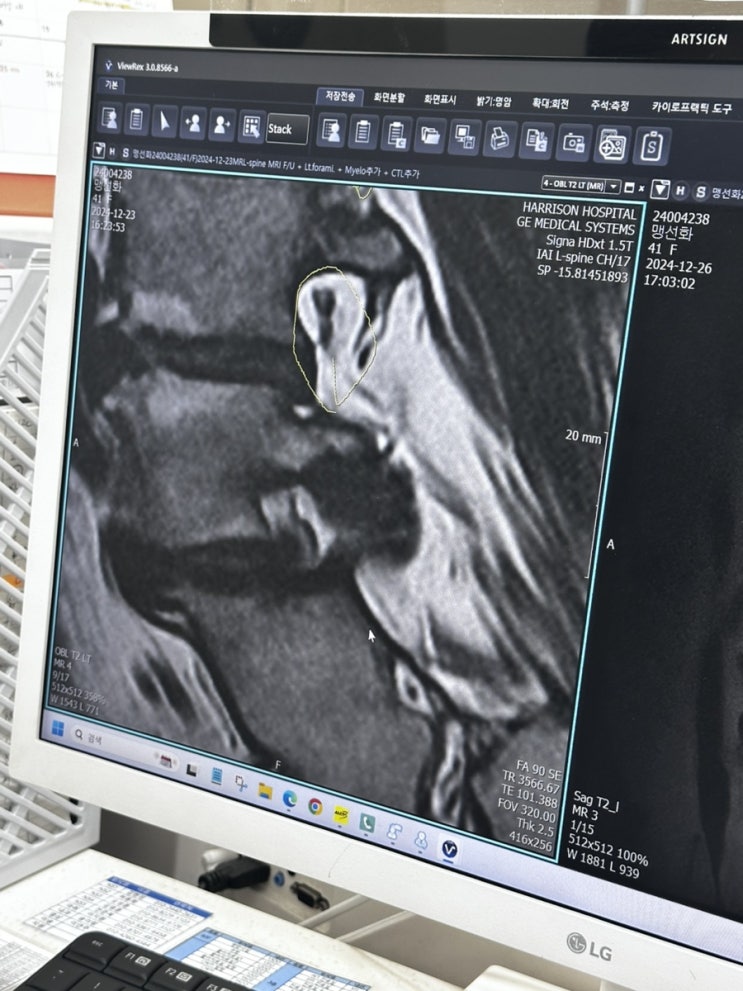

디스크수술...

2024년 12월 24일.. 내가 디스크수술을 했다.. 디스크 5,6 번이 터져서...신경이 마비되는 바람에.. 왼쪽 ...